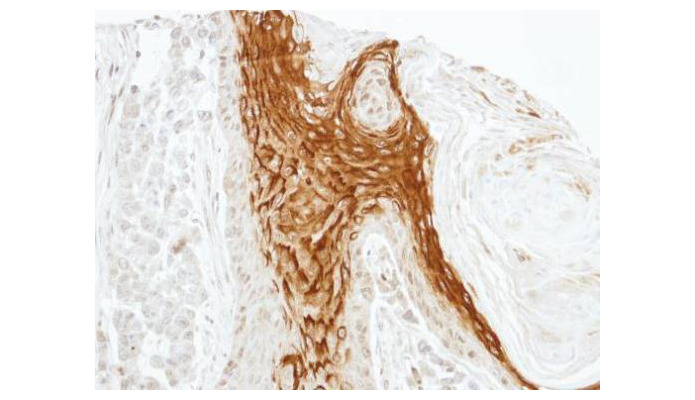

Supportive validation

- Submitted by

- Aviva Systems Biology (provider)

- Main image

- Experimental details

- Immunohistochemical analysis of paraffin-embedded SG xenograft, using RAMP2(OAGA00692) antibody at 1:100 dilution.